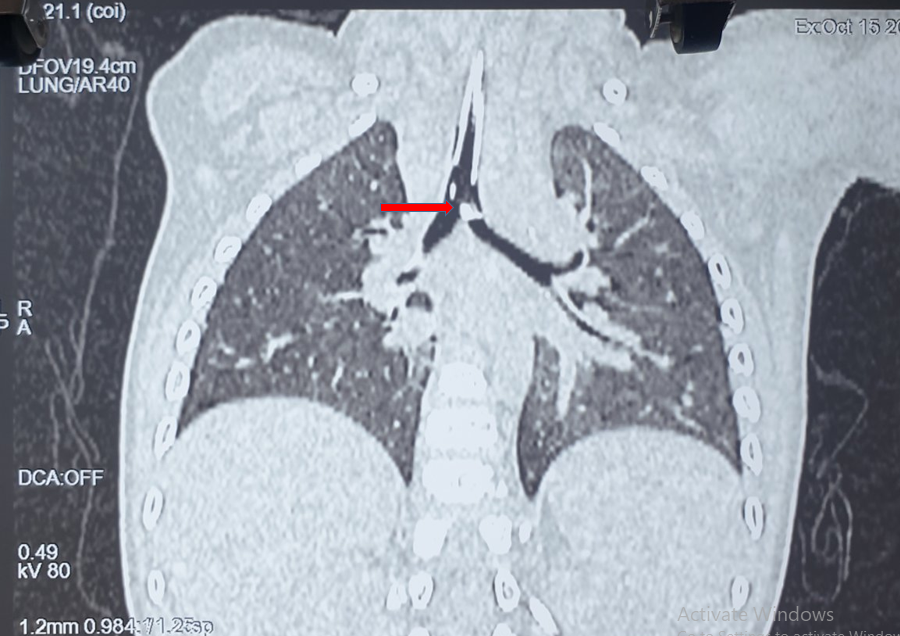

Tại Bệnh viện Nhi đồng Thành phố trẻ biểu hiện khò khè, khó thở, rút lõm ngực, thở gật gù cổ, nhiều đàm nhớt, bứt rứt, tím tái nên được đặt nội khí quản, giúp thở, truyền thuốc dãn phế quản và phun khí dung thuốc dãn phế quản qua máy thở, cũng như sử dụng kháng sinh điều trị viêm phổi. Tình trạng trẻ vẫn không cải thiện nên được hội chẩn chụp CT scan phổi cho thấy hình ảnh dị vật kích thước 0,5x1cm ở ngay chỗ chia đôi khí quản thành phế quản gốc bên phải và trái, hơi nằm chếch bên trái, nên được hội chẩn các chuyên khoa hô hấp, tai mũi họng, tiến hành nội soi đường thở cấp cứu sau khi có test nhanh COVID-19 âm tính.

| Hình ảnh CT scan ngực cho thấy mảnh dị vật |